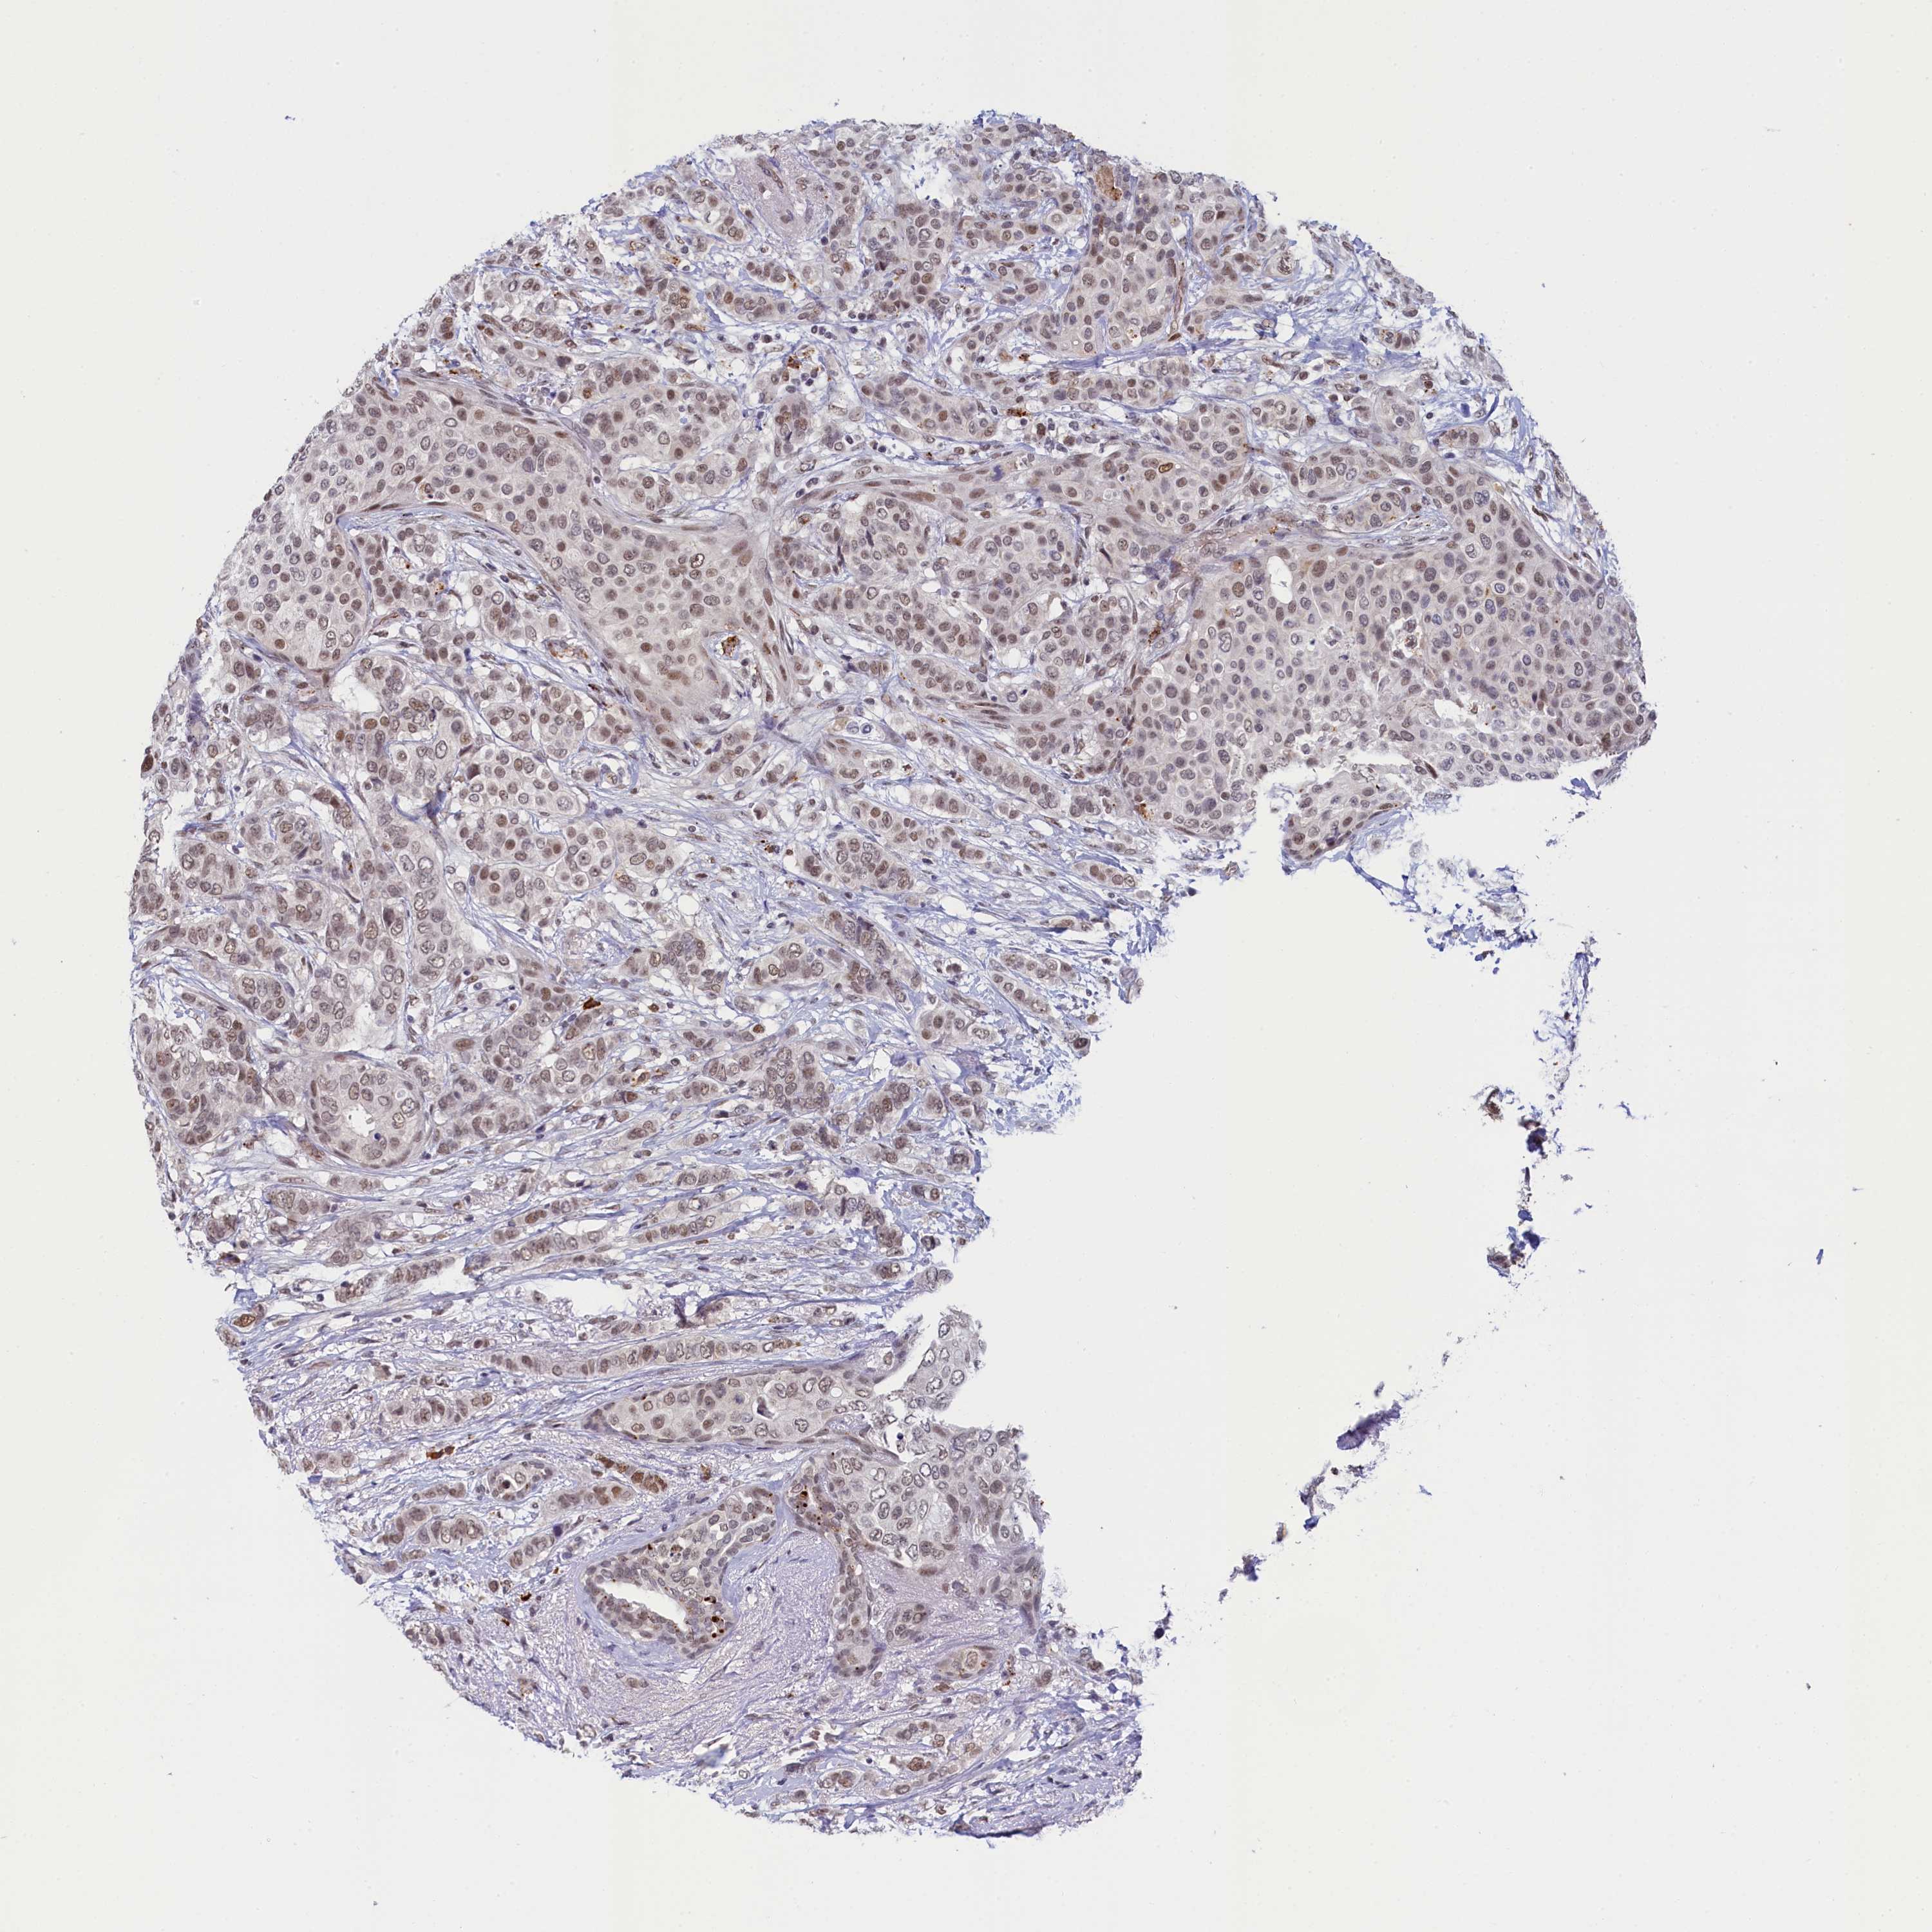

CANCER BREAST CANCER Show tissue menu

BRCA TCGA BRCA VALIDATION PROTEIN EXPRESSION